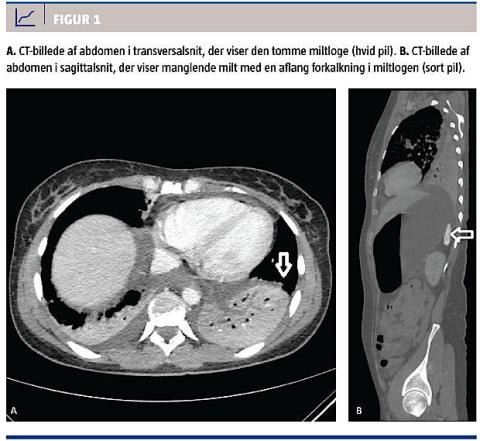

På en CT af thorax og abdomen fandt man et venstresidigt lobært infiltrat, og som bifund konstaterede man manglende milt. På miltens plads sås en 2,4 × 2 cm stor forkalkning (Figur 1). En beskrivelse af en CT-undersøgelse fra tidligere bekræftede, at patienten på daværende tidspunkt havde haft en normal størrelse milt. Autosplenektomien var således udviklet i den efterfølgende periode. Der var forud for indlæggelsen ingen tegn på autosplenektomi, herunder hverken svære infektioner (inkl. pneumokokinfektioner) eller vedvarende trombocytose som tegn på manglende miltfunktion [2]. Hun havde gennem